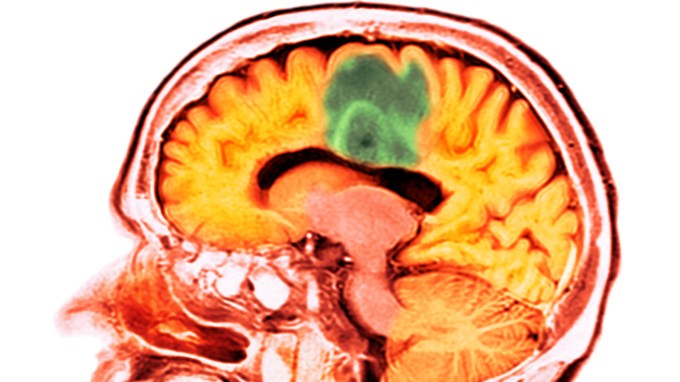

9. Health & Medicine

Ultrasound allows a chemotherapy drug to enter the human brain

An early-stage clinical trial demonstrates a technique for getting a powerful chemotherapy drug past the usually impenetrable blood-brain barrier.